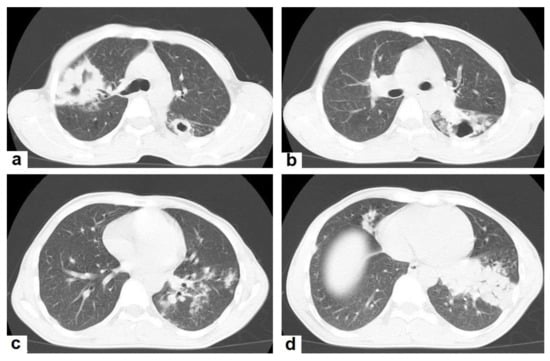

Figure 3. Post primary TB in a 45-year-old male with cough and hemoptysis. Axial images of chest CT show (a) cavitary lesions in the right upper lobe and upper segment of the left lower lobe surrounded with consolidation, (b) cavitary lesion in the upper segment of the left lower lobe with thick irregular wall surrounded by patchy ground glass opacities, (c) centrilobular nodules and tree-in-bud nodules, and (d) consolidation in the left lower lobe with air-bronchograms.

• Consolidation (Figure 3) is considered to be one of the most common features of postprimary TB, which is usually focal, patchy heterogeneous, or poorly defined. It involves the apical and posterior segments of the upper lobes and the upper segments of the lower lobes [10]. Consolidation with ipsilateral enlarged hilar or paratracheal LNs could strongly suggest TB. CT is better able to detect small and subtle TB consolidations, which are usually peribronchial or subpleural and involve multiple lung segments [13].

• Cavitation (Figure 3 and Figure 4) is a common finding in postprimary TB, and it is characterized as being several centimeters in size with thick irregular walls. Cavities are often seen within consolidation and may persist after treatment predisposing to a bacterial or fungal superinfection or adjacent vascular erosion causing hemoptysis [1,10]. In postprimary TB, both consolidation and cavitation have a predilection for the apical and posterior segments of the upper lobes and the upper segments of the lower lobes [1,14]. This predilection of TB is attributed to the relative over-ventilation, high oxygen tension, and delayed lymphatic clearance in these regions [16]. Thick wall cavities are an important differential diagnosis of a pulmonary abscess, septic emboli, aspergilloma, granulomatosis with polyangitis (Wegener’s granulomatosis), lung malignancy, and others [17].